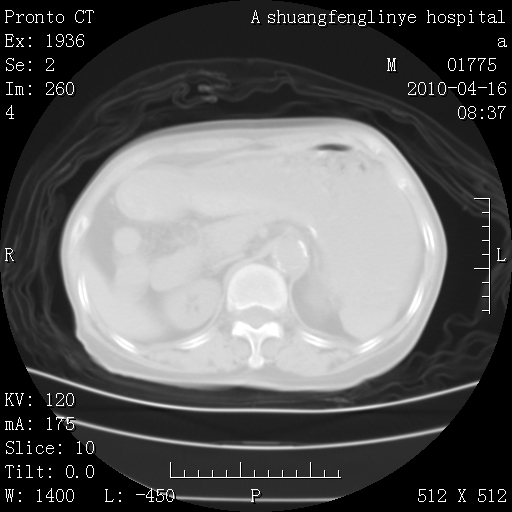

陈旧性结核,胃腔扩大,脾脏受压后移

典型 夹层动脉瘤。 内膜瓣钙化移位